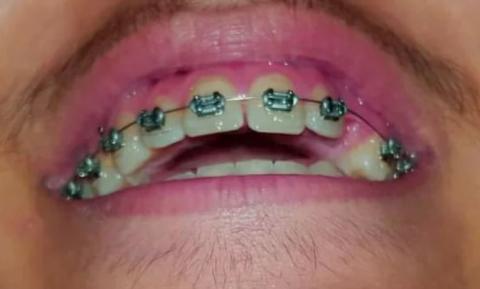

This image shows a patient undergoing upper arch orthodontic treatment with fixed metal braces. The gum tissue above the brackets appears red and inflamed, especially around the front teeth. The appearance is consistent with gingival irritation associated with orthodontic appliances, commonly seen during active tooth movement and plaque retention phases.

Upper anterior and posterior teeth fitted with orthodontic brackets

Archwire engaged across the upper arch

Lower teeth partially visible without braces

No visible tooth fractures or obvious decay

Primary concern involves gingival tissue response, not tooth structure

Redness and mild swelling of upper gingiva

Brackets positioned close to gum margins

Teeth in active alignment phase

No visible pus, abscess, or ulceration

Lips and surrounding tissues appear intact